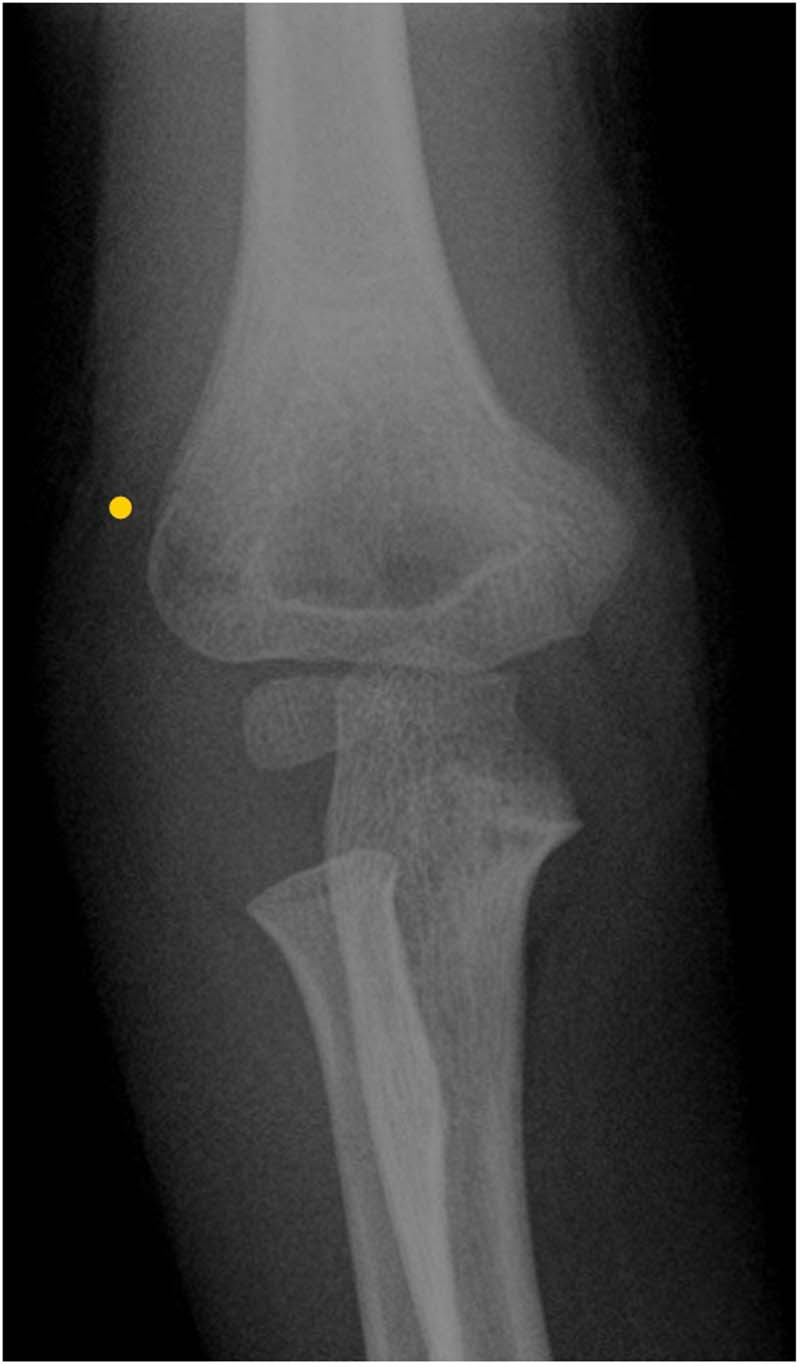

在过去两年中,患儿发生了三次上肢骨折:右侧(图1)和左侧(图2)肱骨髁上骨折,以及右侧肱骨内侧髁骨折(图3)。所有骨折均由家中或学校发生的轻度至中度外力创伤所致,且均与体育运动无关。骨折在经过4-5周的石膏固定后愈合,无后遗症。无骨痛、腹痛、排尿或排便习惯改变或其他全身性症状,也无提示儿童虐待的体征。

图1